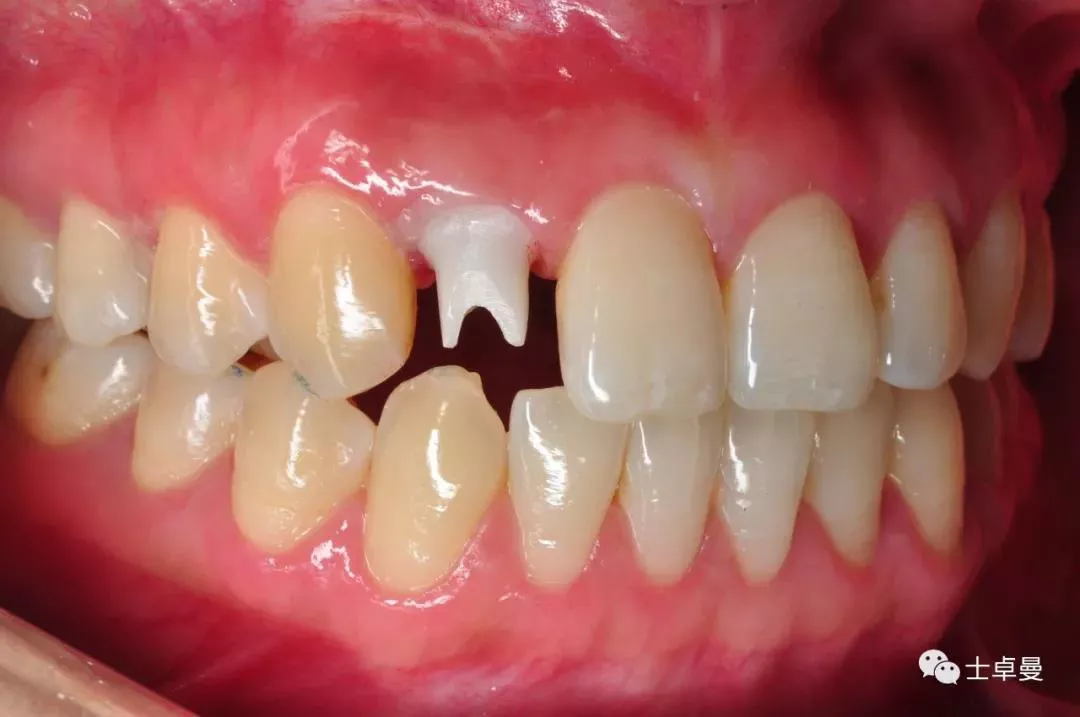

口内检查

·        12残根,断根位于唇侧位于牙龈下1mm,舌侧斜行折裂至龈下3mm-4mm;

术前口内照

断根舌侧劈裂至龈下3mm-4mm

·        唇侧龈缘曲线完好,与邻牙协调,牙龈质地健康,无炎症,薄龈型;

·        残根不松,叩诊不适;

·        11、21之间有约1mm-1.5mm缝隙;